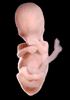

Human Embryo

Carnegie Stage 23 (56 post-ovulatory days)

Most embryos at stage 23 are approximately 56-57 postovulatory days old and measure 23-32 mm in length. Distinguishing criteria for this stage include fusion of the eyelids at the medial and lateral margins, clear distinction of the subdivisions of the upper and lower limbs, the forearms appear at or above the level of the shoulders, the superficial vascular plexus of the head is very close to the vertex, and the external genitalia are well developed but not always sufficiently to distinguish the embryo's sex.

(NOTE: These specimens are late stage 23.)